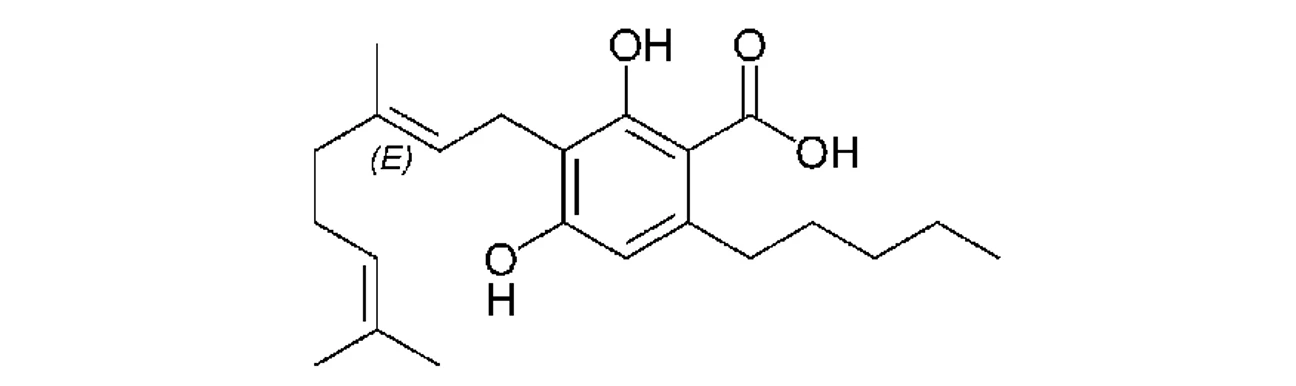

PČR: Kyselina kanabigerolová (CBGA)

PČR: Kyselina kanabigerolová (CBGA)

Biosyntéza (Obr. 5) začíná vytvořením dvou kanabinoidních prekurzorů – geranyldifosfátu a olivetové kyseliny, které spolu kondenzují za účasti geranyltransferasy a vzniku kanabigerolové kyseliny (CBGA). CBGA se následně transformuje na tetrahydrokanabinolovou kyselinu (THCA), kanabidiolovou kyselinu (CBDA) a kanabichromenovou kyselinu (CBCA) pomocí THCA synthasy, CBDA synthasy a CBCA synthasy. Tetrahydrokanabinol (THC), kanabidiol (CBD), kanabigerol (CBG) a kanabichromen (CBC) vznikají dekarboxylací ze svých kyselin během skladování vlivem tepla a světla za uvolnění CO211. THC a iso-THC mohou také vznikat kysele katalyzovanou cyklizací CBD vytvořením příslušných karbokationtů na C-8 a C-1 CBD skeletu (25).

PČR: Obr. 5 – Biosyntéza kanabinoidů a hlavní rozkladné produkty THC (8)

PČR: Obr. 5 – Biosyntéza kanabinoidů a hlavní rozkladné produkty THC (8)